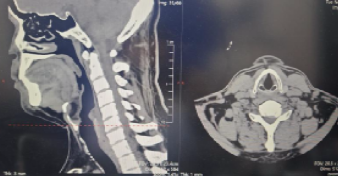

患者为 50 岁男性,3 个月前无明显诱因出现左上臂外侧、前臂背侧麻木胀痛,伴颈肩部酸痛不适,偶有行走不稳症状。在外院就诊时,颈椎 MR 检查提示 “颈椎生理曲度变直,颈椎增生,颈 6-7 终板变性,颈6-7椎间盘突出神经受压”,经保守治疗后症状无改善,为寻求进一步精准治疗来到我院。

入院后,骨科团队为患者进行了详细查体,发现其颈椎生理曲度变直,左侧颈肩部肌肉压痛阳性,左前臂背侧感觉减退,四肢肌力虽正常,但神经根受压症状明确,结合影像学检查结果,最终确诊为 “神经根型颈椎病”。考虑到患者保守治疗效果不佳,且症状已影响生活质量,患者较轻,团队经充分评估后,决定摒弃传统前路开放融合手术,采用后路微创内镜技术为其实施减压。